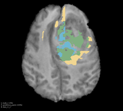

Deep neural network models used for medical image segmentation are large because they are trained with high-resolution three-dimensional (3D) images. Graphics processing units (GPUs) are widely used to accelerate the trainings. However, the memory on a GPU is not large enough to train the models. A popular approach to tackling this problem is patch-based method, which divides a large image into small patches and trains the models with these small patches. However, this method would degrade the segmentation quality if a target object spans multiple patches. In this paper, we propose a novel approach for 3D medical image segmentation that utilizes the data-swapping, which swaps out intermediate data from GPU memory to CPU memory to enlarge the effective GPU memory size, for training high-resolution 3D medical images without patching. We carefully tuned parameters in the data-swapping method to obtain the best training performance for 3D U-Net, a widely used deep neural network model for medical image segmentation. We applied our tuning to train 3D U-Net with full-size images of 192 x 192 x 192 voxels in brain tumor dataset. As a result, communication overhead, which is the most important issue, was reduced by 17.1%. Compared with the patch-based method for patches of 128 x 128 x 128 voxels, our training for full-size images achieved improvement on the mean Dice score by 4.48% and 5.32 % for detecting whole tumor sub-region and tumor core sub-region, respectively. The total training time was reduced from 164 hours to 47 hours, resulting in 3.53 times of acceleration.